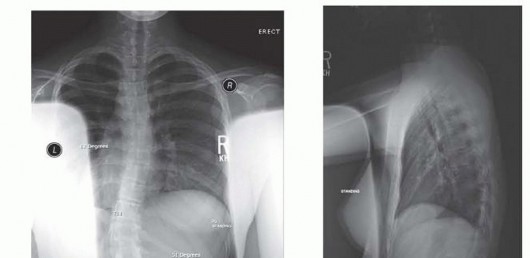

Modified Woodward Repair of Sprengel Deformity DEFINITION Sprengel deformity is a congenital anomaly of the s…